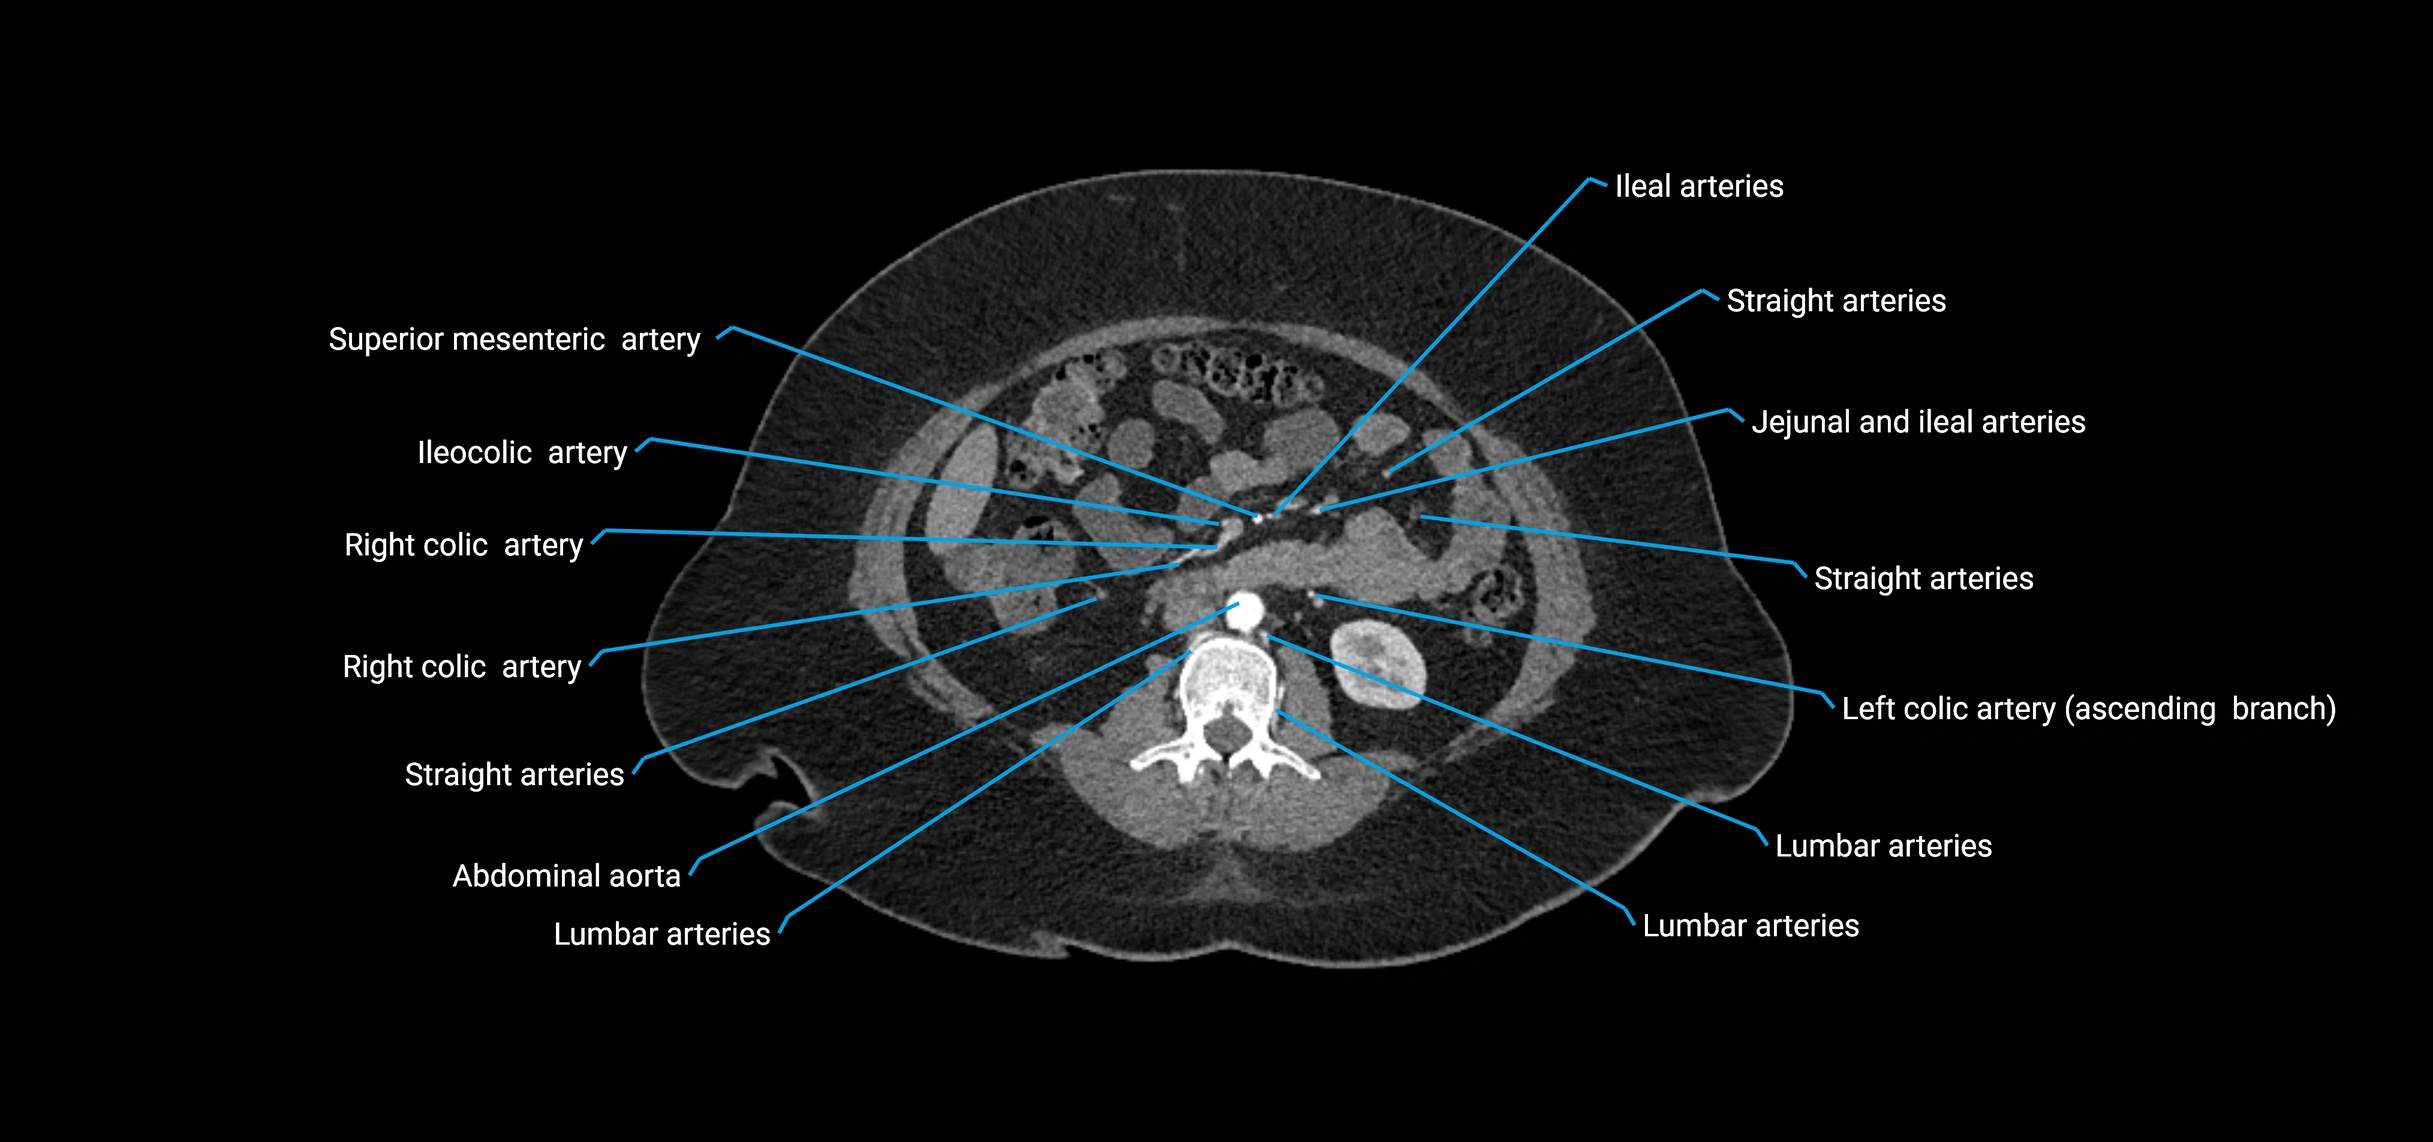

Contrast-enhanced CT (CTA):

• Gold standard for abdominal aortic imaging

• Provides excellent detail of lumen, wall, aneurysm, thrombus, and branch vessels

• Multiplanar and 3D reconstructions help in aneurysm measurement, stent graft planning, and dissection evaluation

• Detects acute rupture, traumatic injury, or occlusion with high sensitivity